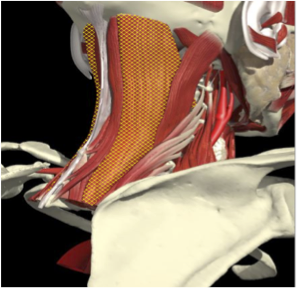

LATEROCAPUT

Muscles that insert into skull (mastoid/ occiput)

- Trapezius

- Sternomastoid

- Splenius capitus/cervicus

- Levator scapulae

- Longissimus capitus

Range of movement

- 8 degrees